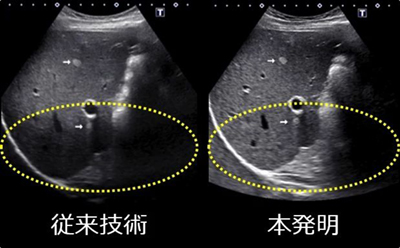

川岸氏はこれらの問題を克服するため,周波数が異なる2種類の超音波を同時に送信し,反射波において第2高調波と第2高調波と同じく非線形効果により生じた差周波の合成波を発生させる超音波診断装置を開発した。この合成波は,非線形効果による反射波の成分のみから構成され,低周波数から高周波数までを網羅する広い周波数帯域の超音波である。そのため,超音波診断装置において映像におけるアーチファクトが少ないという従来技術の良さを残したまま,浅部から深部にかけて十分な感度を持つ高分解能な映像を得ることを可能にした。

本開発により,従来技術では超音波診断が困難であった部位(消化管,皮膚,関節,筋,腱,骨等)における超音波診断確立に寄与している。また,従前超音波診断が行われていた部位(肝臓,胆嚢,膵臓,乳腺,甲状腺,前立腺,子宮,卵巣等)についても病変の早期発見・早期治療開始が可能となった。同社製の超音波診断装置のラインアップには「D-THI(Differential Tissue Harmonic Imaging)」として本技術を搭載し,世界中の医療に貢献している。